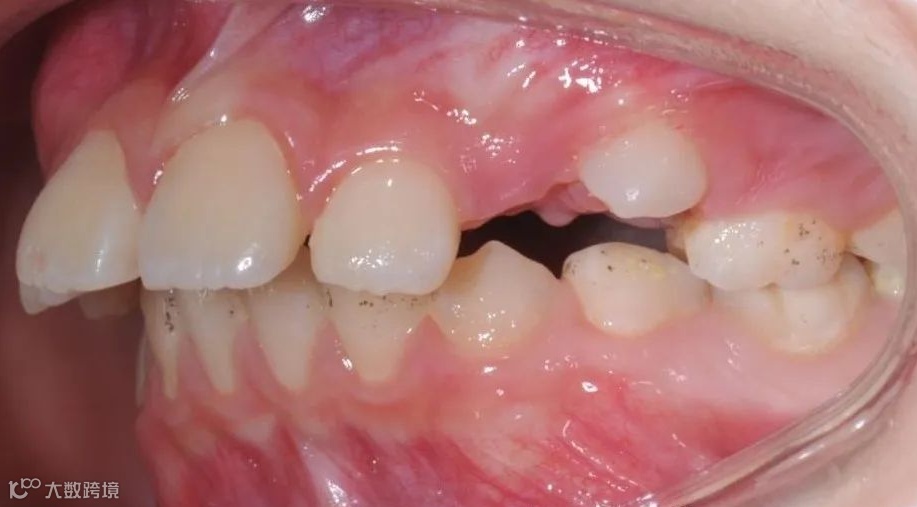

治疗前右侧咬𬌗相

治疗前正面向咬𬌗相

治疗前左侧咬𬌗相

患儿戴用Twin-Block矫治器,在引导下颌向前的同时扩宽上颌牙弓,内收上前牙。